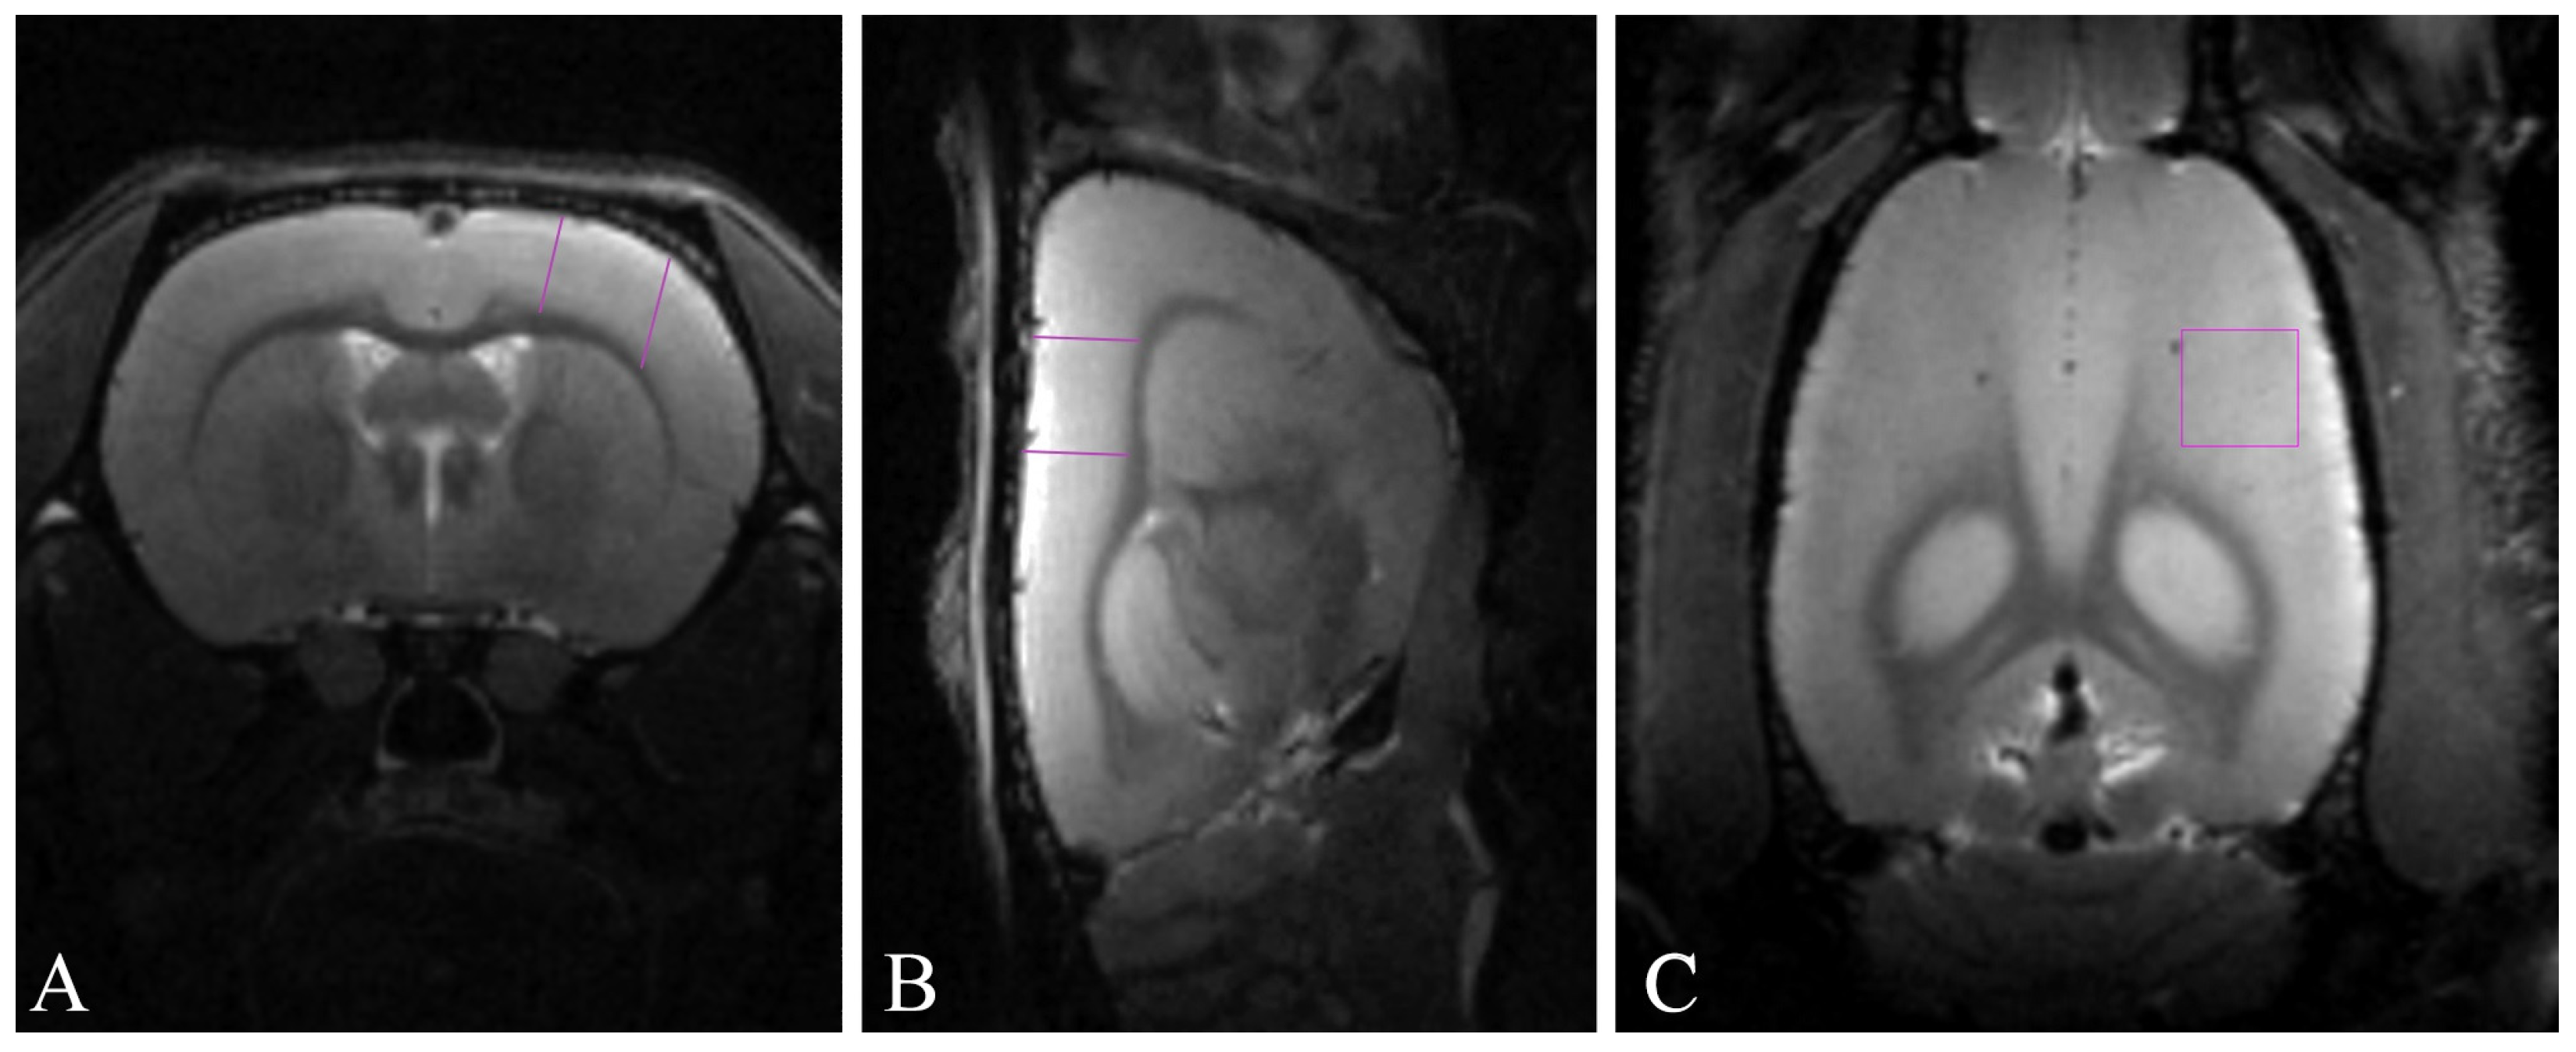

4.5. Magnetic Resonance Imaging-Based Morphometry